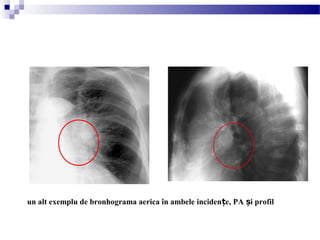

un alt exemplu de bronhograma aerica în ambele inciden e, PA i profilț ș